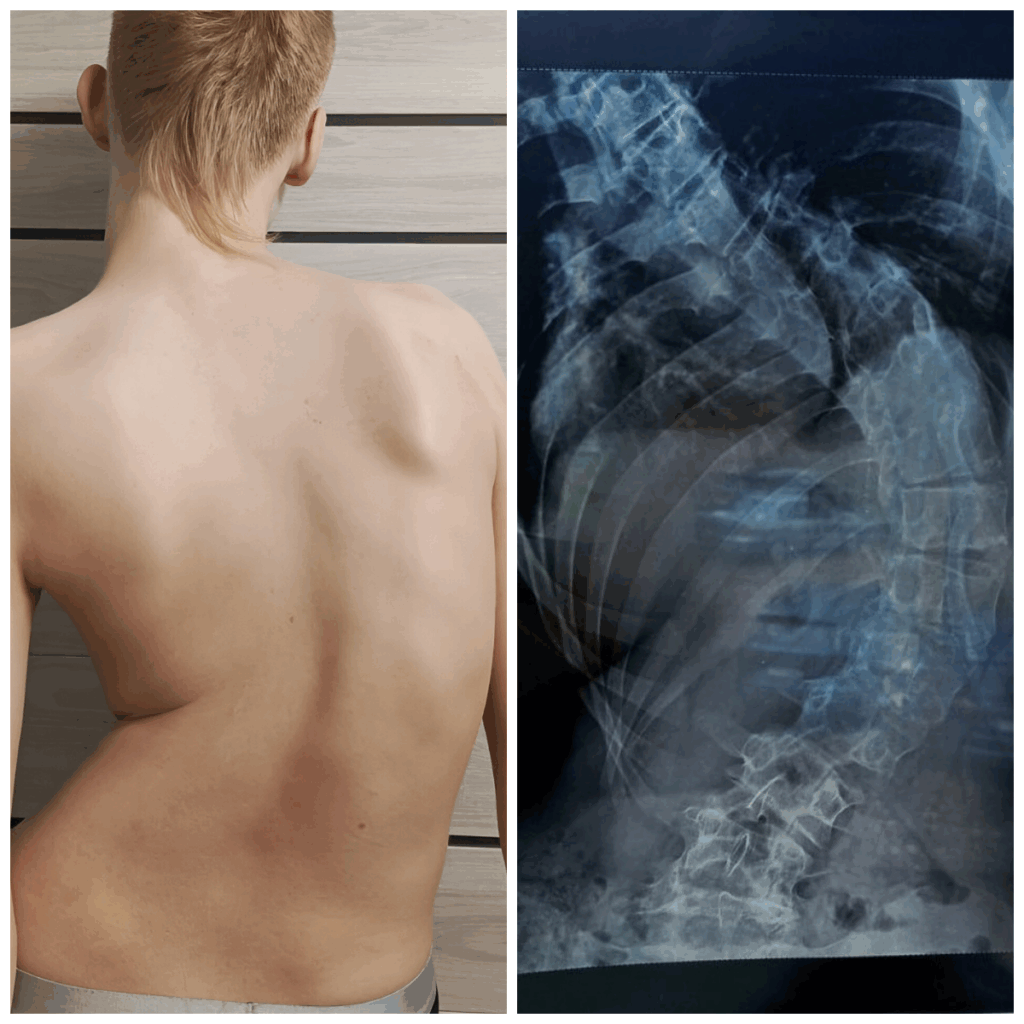

В 11 лет у Сережа стал жаловаться на головокружения и плохую координацию движений. Врачи успокаивали: «Такое бывает из-за активного роста ребенка». Предлагали «подождать, пока перерастет». Но рост костей у Сережи опережал мышечный рост. Началась деформация позвоночника. «Одно плечо заметно ушло вниз». Подростку поставили очередной диагноз — юношеский идиопатический сколиоз — и рекомендовали постоянно носить лечебный корсет Шено. Даже спать в нем.

К сожалению, остановить быстро прогрессирующий сколиоз не удалось. У Сережи появился реберный горб в 4 сантиметра. Сейчас даже небольшая физическая нагрузка или просто изменение положения тела вызывает боль в спине. Подростку тяжело нагибаться, он с трудом надевает брюки и завязывает шнурки. Внутренние органы оказались зажаты и спустились ниже, появилась одышка.

Сергея осмотрели врачи и, «учитывая крайне выраженную степень и прогрессирующий характер деформации», рекомендовали хирургическое лечение. Тянуть нельзя. Установить специальную металлоконструкцию на позвоночник необходимо до того, как начнутся необратимые процессы — будет нарушена чувствительность в теле и появятся сосудистые нарушения.